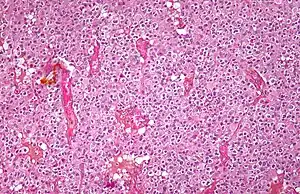

Cuando hay células con forma de "huevo frito", es seguro que se trata de un oligodendroglioma.